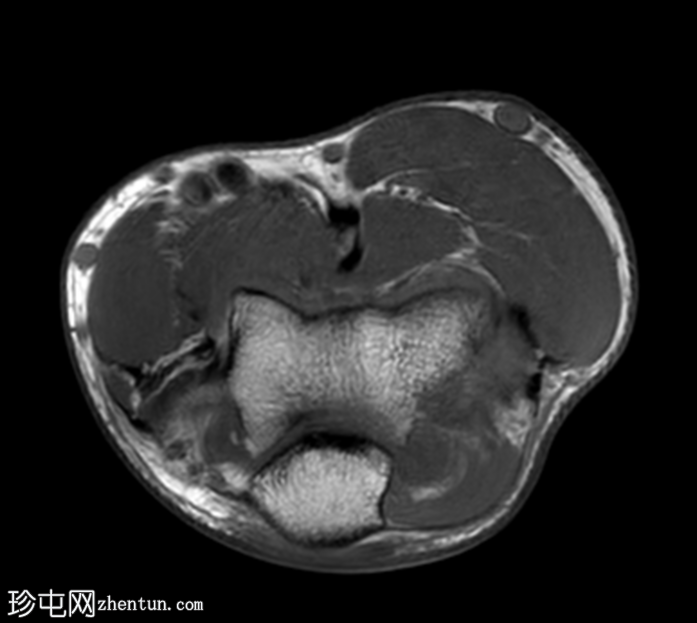

轴位PD加权像

脂肪抑制像

桡骨头及桡骨颈可见骨髓水肿,前内侧关节内部分可见低信号骨折线,符合桡骨头无移位骨折。

肱骨远端外侧髁/肱骨小头也可见明显的骨髓水肿。伴有皮质不规则、凹陷及正常轮廓消失,提示骨小梁嵌顿。

位于水肿骨内的这处骨损伤(奥斯本-科特里尔损伤)代表的是真正的撞击性骨折,而非常见的正常解剖假性缺损。

桡骨近端周围存在广泛的软组织水肿和液体信号,提示环状韧带损伤。

另可见大量关节积液。